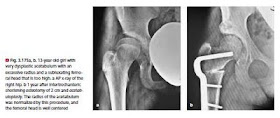

But this assumption now needs to be revised. In recent years we have observed several cases in which a normal hip during childhood has deteriorated into a distinctly dysplastic hip during puberty (⊡ Fig. 3.167).

Evidently, premature closure of the triadiate cartilage can occur during puberty so that the acetabulum no longer adequately matches the growth in size of the femoral head.

! Every treated hip must be monitored radiographically until adulthood. X-rays (AP) should – as a minimum requirement, i.e. if no special features are present – be recorded after the start of walking, at the age of 8–10 years and on completion of growth.